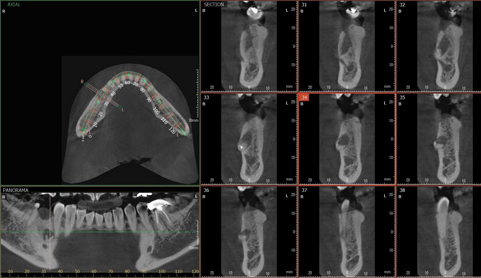

3D CT/파노라마 촬영을 통한 정확한 진단

단순한 치료라도 3D-CT/파노라마을 통해서 체크!

디지털 시뮬레이션을 통한 정확한 식립 위치와 깊이 진단.

정밀한 진단과 치료계획의 수립은 성공적인 임플란트 수술의 시작입니다.

치과는 저방사선 CT/PANO, 카보키레이저, 오스텔멘토, 무통마취기 등 디지털 의료장비를 통해 구강상태와 치조골의 정밀 진단, 전신 상태까지 세밀하게 검사하여 안전한 치료계획을 수립합니다.